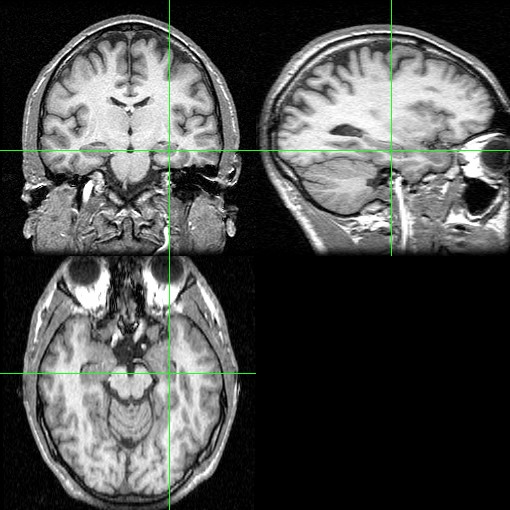

Hipokampus je velmi citlivý vůči vnějším vlivům, jako je stres nebo spánková deprivace, které ho formují zejména v dětství. Odborníci z centra CEITEC a Masarykovy univerzity v Brně, kteří v rámci své studie zkoumali 113 dobrovolníků, respektive s využitím magnetické rezonance zkoumali jejich mozky, přišli na to, že hipokampus u lidí, kteří déjà vu prožívají, je menší.

To může mít podle vedoucího výzkumu profesora Milana Brázdila za následek větší citlivost a spouštění falešných vzpomínek.